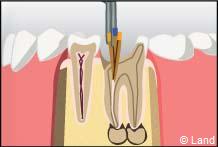

2° Il doit ensuite mettre en forme le canal afin de pouvoir réaliser l’obturation canalaire, le plus souvent à l’aide de gutta-percha chauffée ou froide permettant d’obtenir une étanchéité de bonne qualité afin de prévenir toute ré-infiltration par des bactéries et d’assurer sur le long terme la conservation d’une dent assainie. S’il y avait une lésion infectieuse au bout de la dent, celle-ci guérira, si elle n’est pas déjà trop avancée.

Une fois la dent traitée il peut arriver que, dans les jours suivants, persiste une certaine sensibilité surtout lors de la mastication : cette gêne sera temporaire.

Attention : si la dent est privée de sa sensibilité, elle reste toujours fragile et peut à nouveau se carier. En revanche elle garde ses capacités de sensibilité à la pression grâce au ligament alvéolo dentaire.